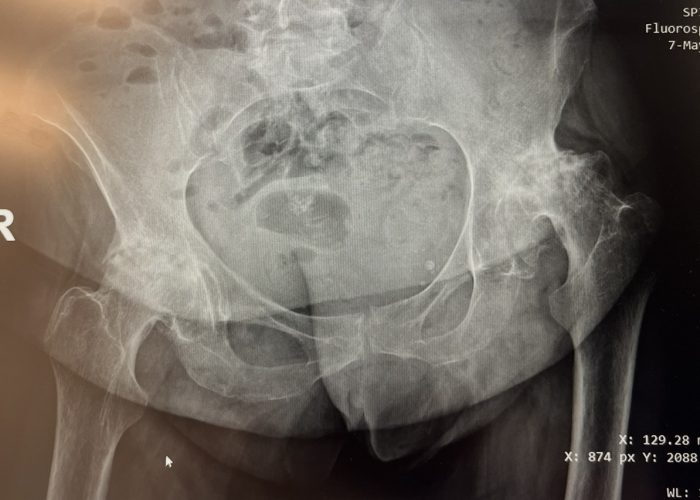

Pacienta, în vârstă de 56 de ani, s-a prezentat cu displazie coxală severă la șoldul stâng și coxartroză avansată la șoldul drept, asociate cu o scurtare a membrului inferior de aproximativ 2 cm.

După o evaluare atentă și planificare chirurgicală individualizată, am decis efectuarea unei artroplastii totale de șold bilateral, în doi timpi operatori, la un interval de aproximativ două luni între intervenții.